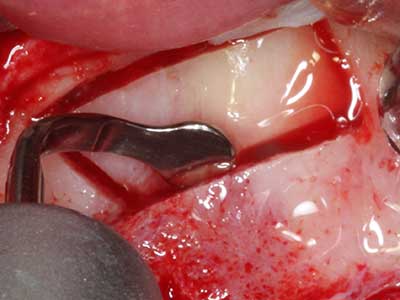

Fig. 18: Preparación de una tapa cortical con la sierra ósea piezoeléctrica (Piezomed, W&H).

Fig. 19: Zona operada después de neurolisis y eliminación del osteomo.

Fig. 20: La tapa ósea extraída se readapta y se fija mediante un tornillo para osteosíntesis (KLS Martin, Tuttlingen).